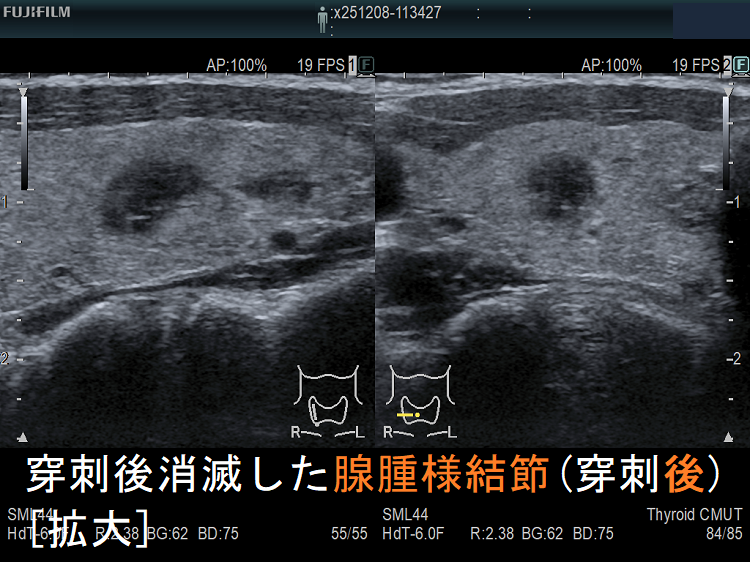

穿刺細胞診後内部融解

![穿刺後消滅した腺腫様結節(穿刺後) [拡大] 穿刺後消滅した腺腫様結節(穿刺後) [拡大]](../images/basic/basic5/images20251216212323.png)